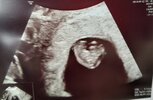

Ja dzisiaj po wizycie 7w 2 d z miesiączki i pokrywa się to idealne z USG.

Całe 1.11 cm człowieczka z serduszkiem ❤️

Termin z USG na 6 maja 2023 r.